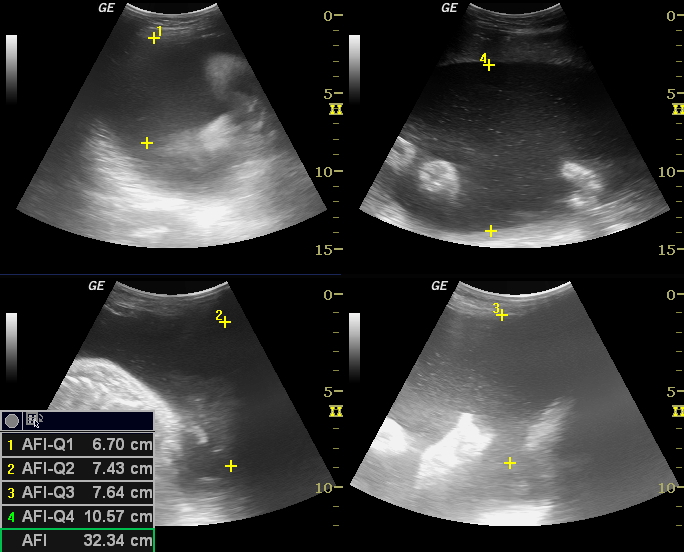

Measurement of amniotic fluid quantity